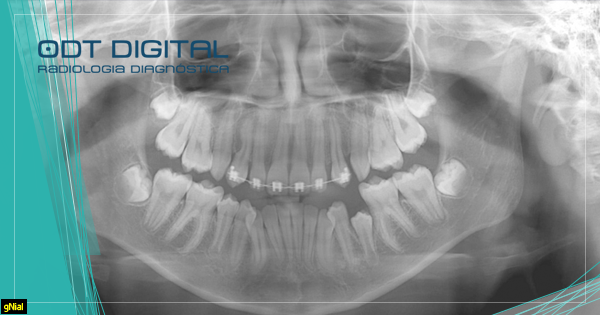

A documentação ortodôntica nada mais é que uma serie de exames e moldes que proporcionam uma visão abrangente do paciente,

Os exames envolvem principalmente moldes para análise da arcada, radiografias e a tomografia computadorizada. A Radiografia Panorâmica Digital permite observar